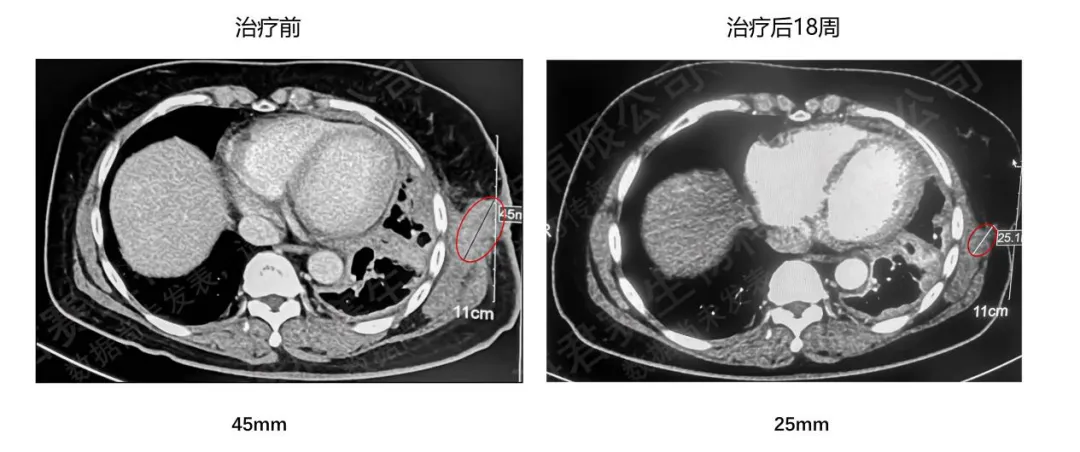

一位晚期肺腺癌合并淋巴结、胸壁、胸膜及骨转移的患者,既往已行放疗及靶向治疗,疾病进展后接受GC101 TIL治疗,18周后复查CT示左侧胸壁病灶明显缩小。

患者治疗前后CT对比图